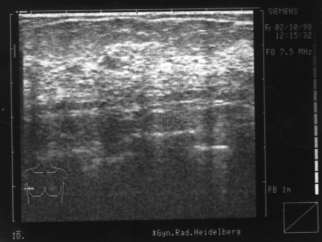

Am Montag kam eine Freundin zu mir, sagen wir, sie heißt Marga (40 Jahre), und war ziemlich aufgelöst. Sie sagte, sie habe einen großen und schmerzhaften Knoten in der linken Brust. Sie war vor ein paar Tagen deshalb bei einer Untersuchung und der Prof. sagte, sie müsse ihn dringend, und zwar so schnell wie möglich, rausnehmen lassen, denn die Gefahr sei groß, daß er streut. Sie selbst hat auch das Gefühl, daß der Knoten bösartig ist. Sie hat das Ultraschallbild und zeigt es mir. Man sieht einen fast runden großen, dunklen Fleck mit vier grauen unscharfen Ausbuchtungen. Marga nennt sie „die vier Ecken“.

Vorher: